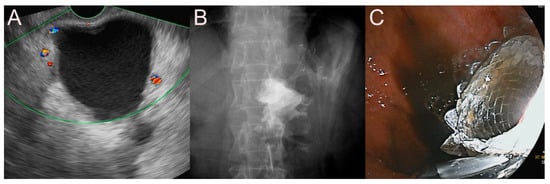

2.3. Stent for EUS-Guided Gallbladder (GB) Drainage

2.3.3. Use of the LAMS